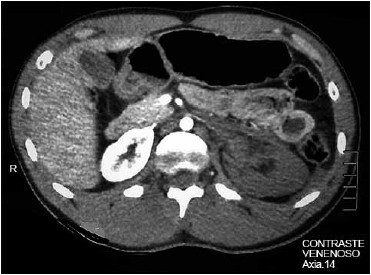

Foi realizado FAST (Focused Assesment with Sonography for Trauma), que detectou líquido livre no espaço de Traube. Foi realizada tomografia de abdome com contraste, cujo laudo revelou lesão do pedículo vascular esquerdo com hemorragia contida (imagem demonstrada a seguir).

(Arquivo pessoal; imagem usada com autorização)

Considerando-se o descrito no enunciado, a imagem apresentada e a classificação mais utilizada e adotada pela AAST (American Association for the Surgery of Trauma), assinale a alternativa que contempla o diagnóstico da lesão renal baseado na classificação da AAST.